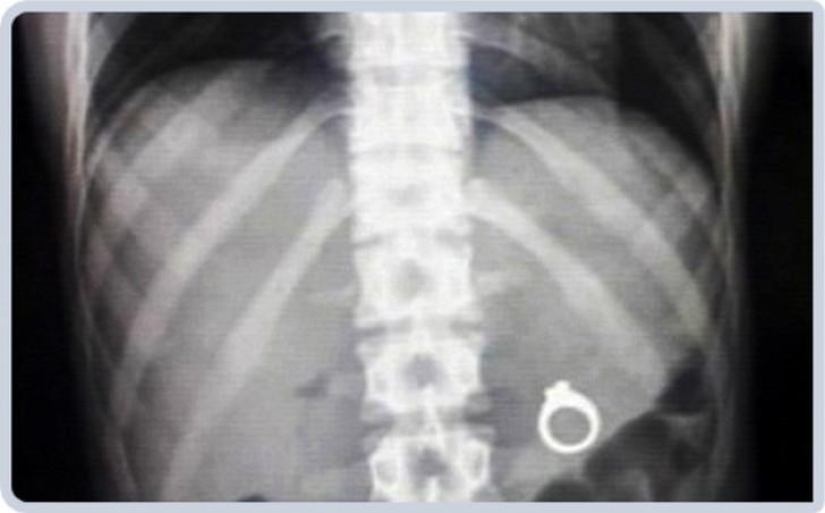

Wedding ring.